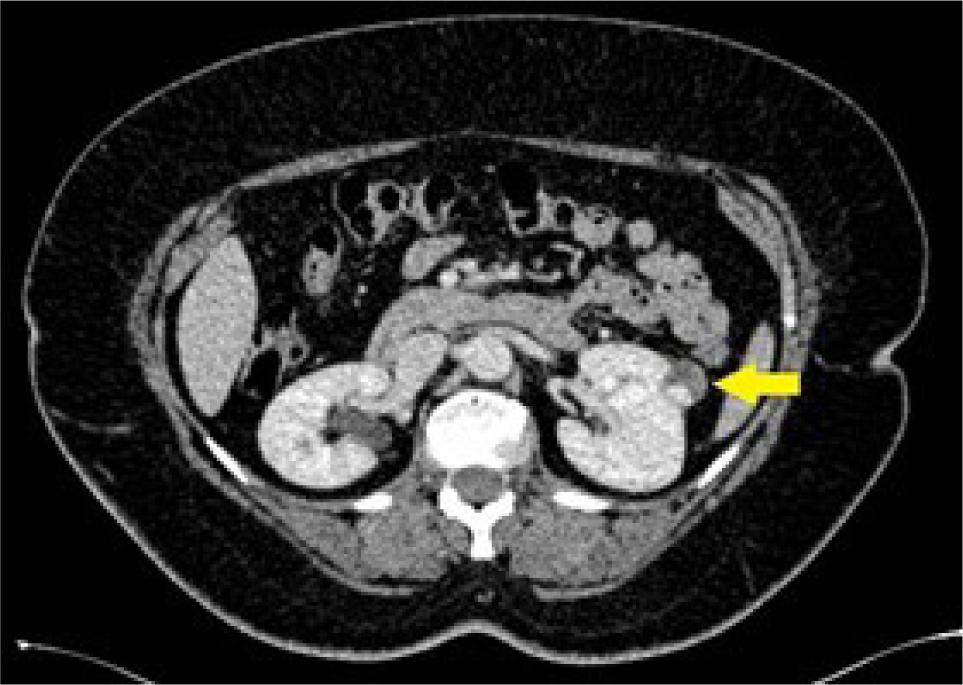

Figure 2: Axial CT at the level of the lower poles of the kidneys in a 43-year-old male showing a 37 mm bi-loculated left renal cyst (yellow arrow) with mild focal enhancing of its wall, categorized as Bosniak IIF cyst, confirmed by no change in size or morphology on 12 months follow-up. The angular interface sign is absent.